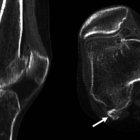

Fabela se llama el hueso que podría estar incrustado en el tendón que está detrás de la rodilla y que sería la causa de muchos dolores.